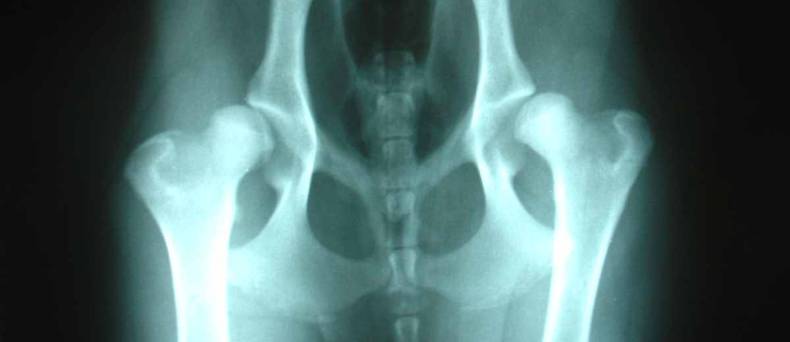

De klinische tekens in combinatie met het ras van de hond, zullen in veel gevallen al een vermoedelijke diagnose opleveren. Deze kan bevestigd worden door radiografie.

foto: Kalumet, X-ray image of an isolates processus anconaeus in a 5 year old German shepherd dog, resized and cropped, CC BY-SA 3.0Osteoarthritis in DogsArthritis in Dogs